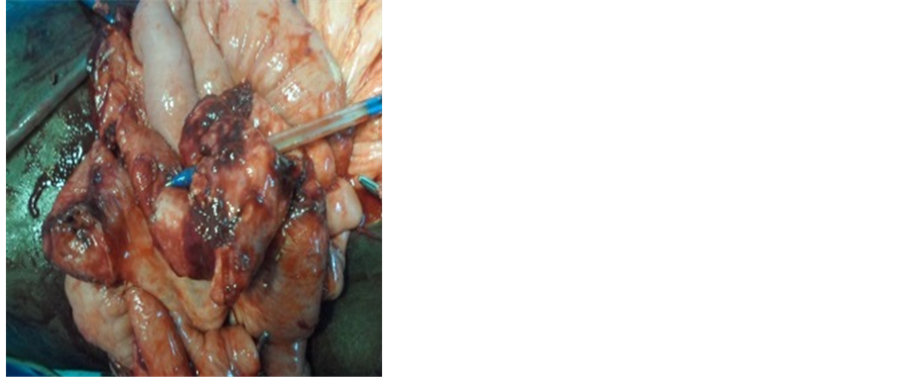

explorative laparotomy was performed. After opening the abdomen we aspirated 300 cc of purulent peritoneal fluid. Exploration had found an agglutination of small bowel loops around the ballpoint pen. The ballpoint pen was about 13.5 cm long and was transfixing the small intestine (Figure 3). We had noted about 20 cm of ileal necrosis located about 30 cm from the ileocecal junction. The ballpoint had perforated the posterior bladder wall (Figure 4). We performed a resection of the necrotic portion of the ileum followed by end-to-end anastomosis (Figure 5). The bladder perforation was closed in two layers, and a urinary catheter was placed. Antibiotics

Figure 3. Agglutination of bowels around the pen.